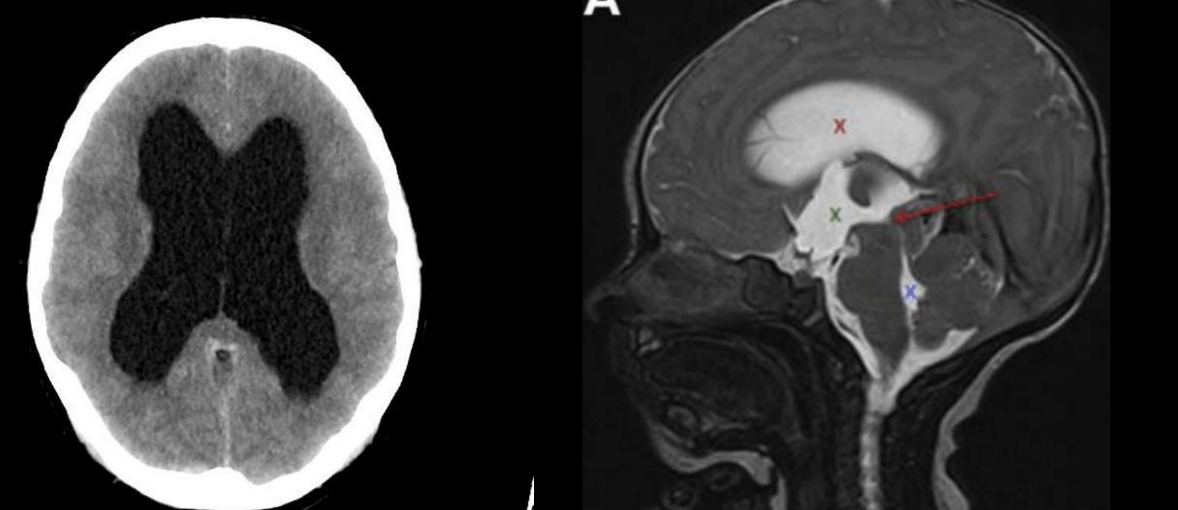

Causa más común

Estenosis acueductal